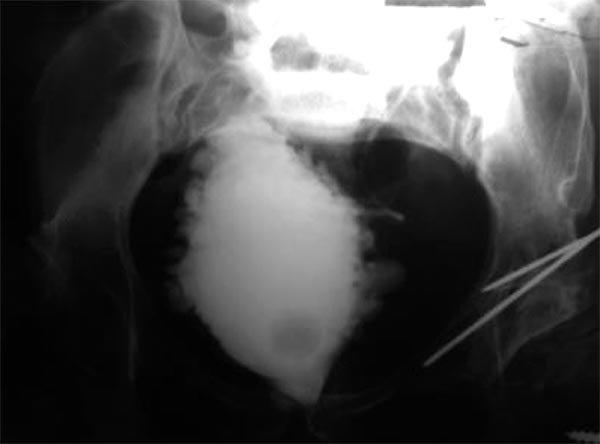

Paciente de sexo femenino de 34 años de edad con MMC Grado 3. Defecto del tubo neural corregido a las 6 horas de vida e hidrocefalia tratada con una derivación ventriculoperitoneal a los 12 meses de vida. No efectuaba cateterismo. Urograma excretor: normal. Incontinencia fecal y urinaria. Siempre uso pañales. A los 22 años de edad se realizó cistografía retrógrada con resultado patológico (fig. 2).

- En la actualidad: lleva pañales, sin cateterización (fig. 2).

Figura 2: Cistografía paciente n°3.

- Cistouretrografia: divertículos, paredes vesicales severamente comprometidas (fig. 3).

Figura 3: Cistografía paciente n°5.

- Vejiga de lucha que presenten divertículos (figs. 1-3).